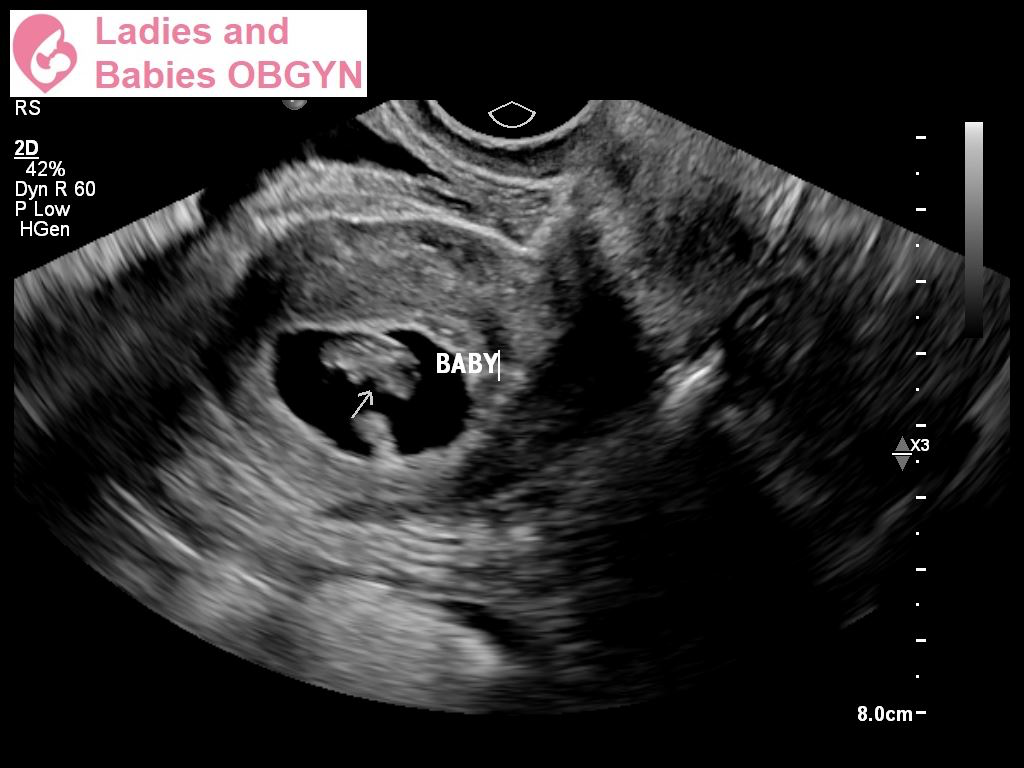

Just had our first ultrasound! They said everything looks great! Healthy heartbeat of 175. Gave us a due date of March 18. can’t wait to see the little bean grow 💜🌈✨